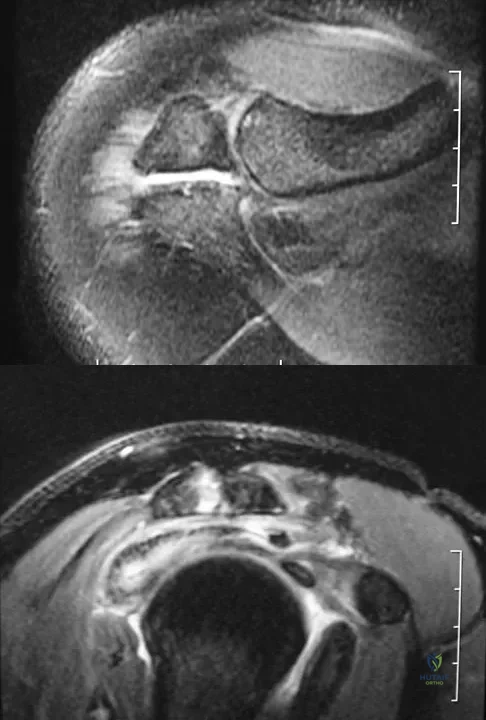

Figures 34a and 34b show the axial and sagittal MRI scans of a 36-year-old man who reports the insidious onset of pain in the right shoulder. What is the most appropriate description of the acromial morphology?

Explanation